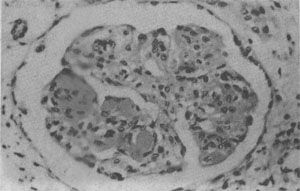

图4-10 狼疮性肾小球肾炎 肾小球毛细血管丛节段性纤维素样坏死,伴系膜细胞增生;间质炎细胞浸润 (2)皮肤:约40%的SLE病人有明显皮肤损害,以面部蝶形红斑最为典型,亦可累及躯干和四肢。镜下,表皮常有萎缩、角化过度、毛囊角质栓形成、基底细胞液化,表皮和真皮交界处水肿,基度膜、小动脉壁和真皮的胶原纤维可发生纤维素样坏死,血管周围常有淋巴细胞浸润。免疫荧光证实真皮与表皮交界处有IgG、IgM及C3的沉积,形成颗粒或团块状的荧光带即“狼疮带”,可能是坏死上皮细胞释出之抗原与血循环中弥散出来的抗核抗体等自身抗体形成的免疫复合物。狼疮带的出现对本病有诊断意义。 (3)心:大约半数病例有心脏受累,心瓣膜非细菌性疣赘性心内膜炎(nonbacterial verrucous endocarditis或Libman-Sach endocarditis)最为典型,敖生物常累及二尖瓣或三尖瓣,其特点为:大小自1mm至3~4mm,数目单个或多个不等,分布极不规则,可累及瓣膜之前后面或心腔之内膜或腱索(图4-11)。镜下,赘生物由纤维蛋白和坏死碎屑及炎症细胞构成,根部基质发生纤维素样坏死,伴炎细胞浸润,后期发生机化。